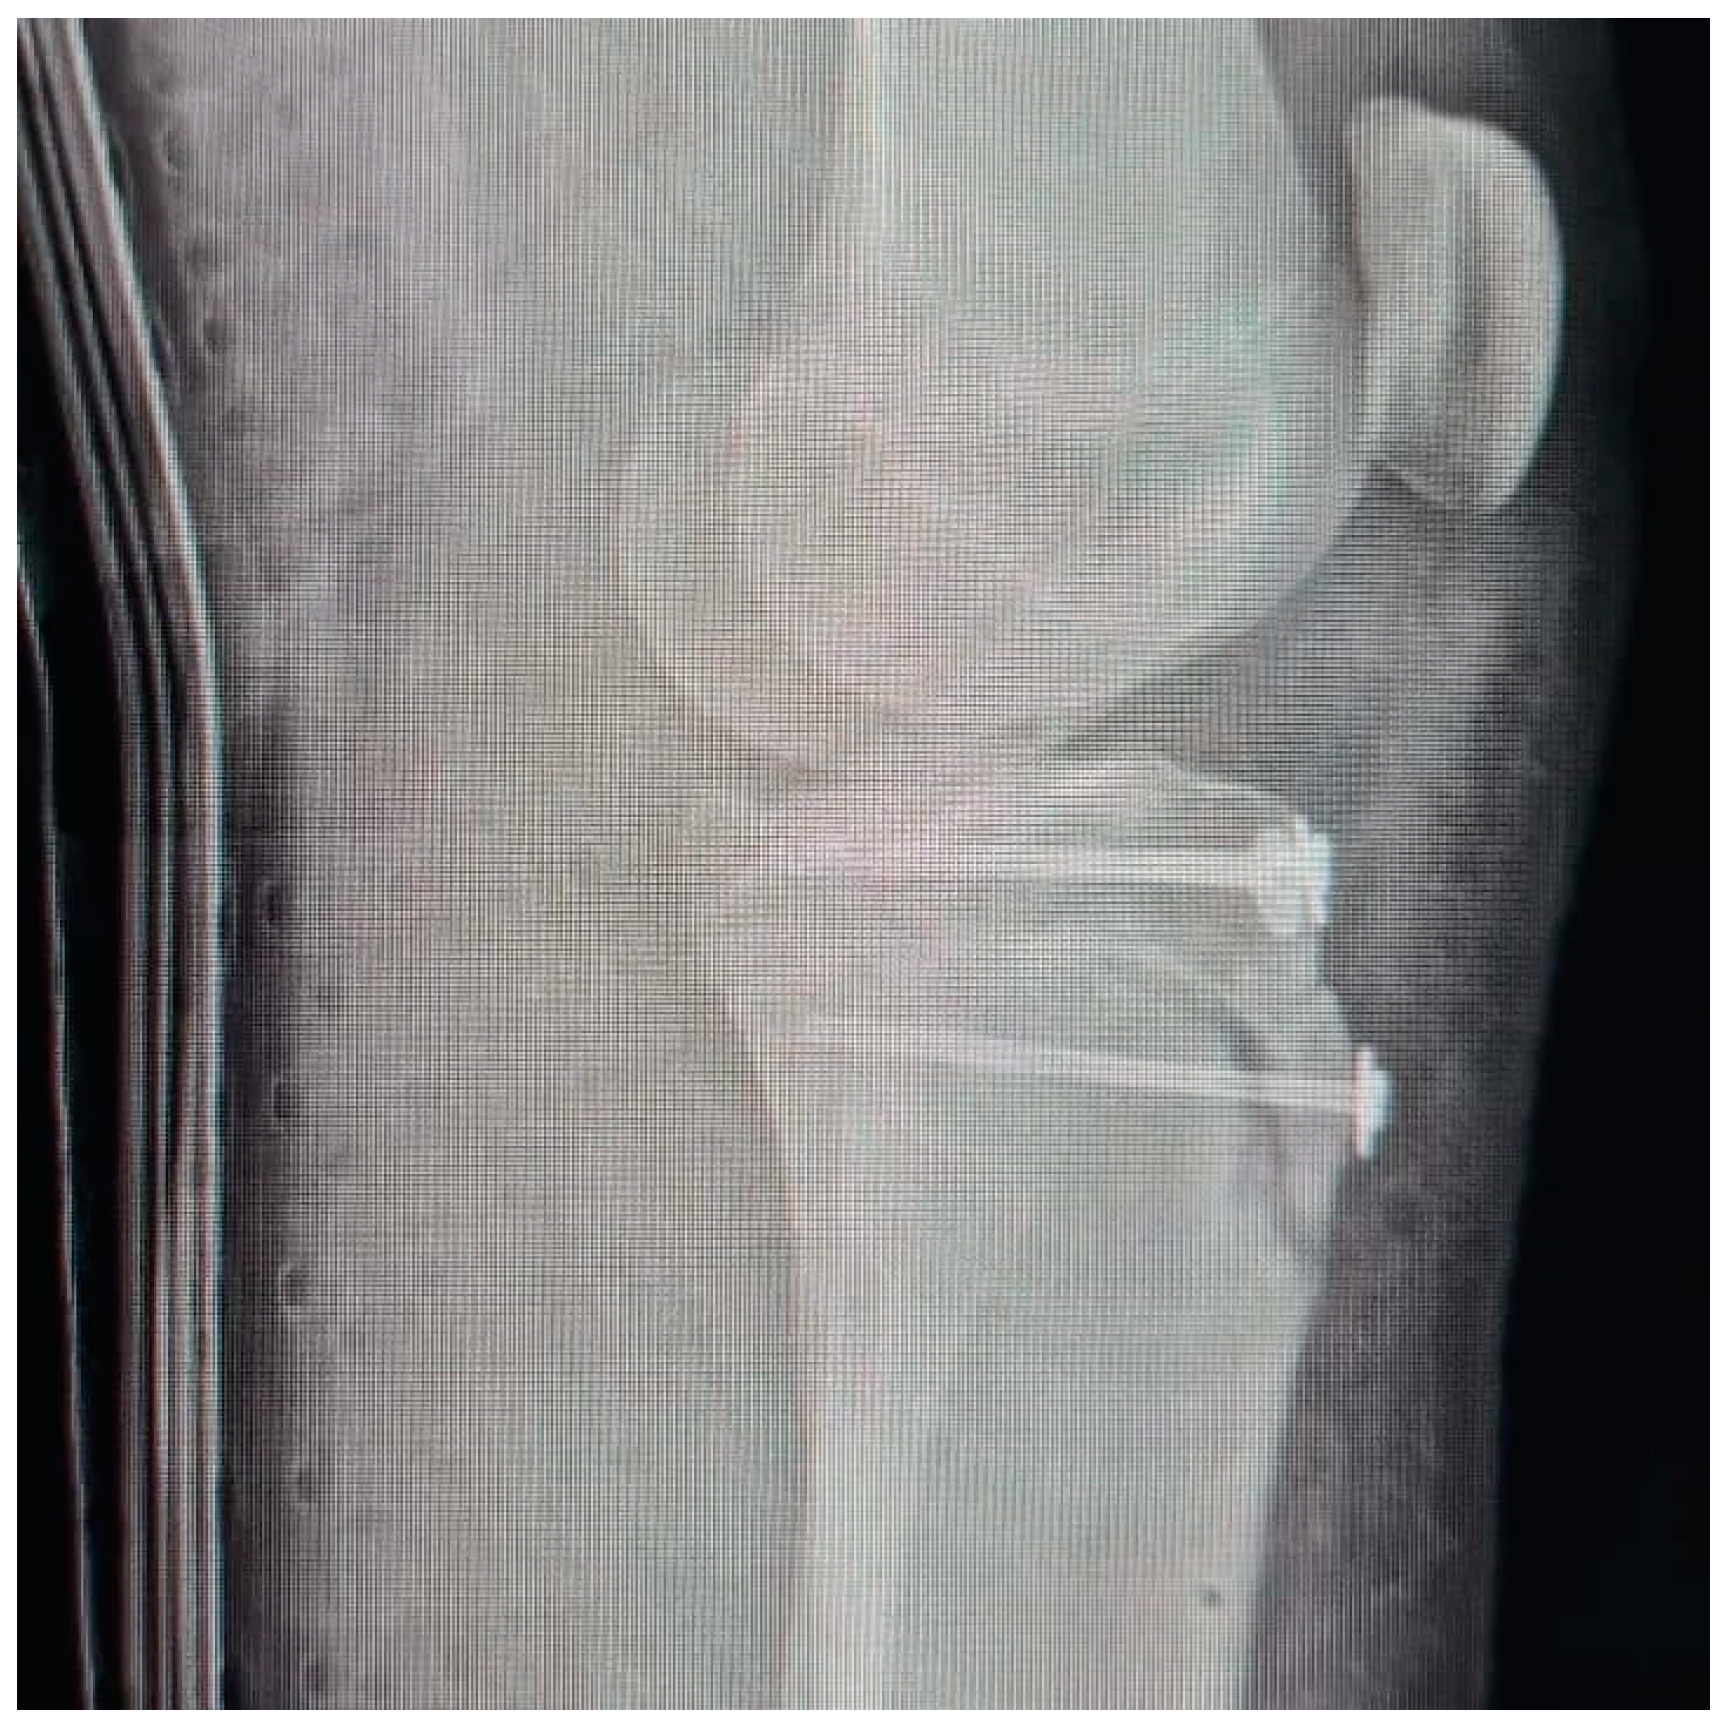

Tibial Tubercle Avulsion Fracture in Young Athletes Surgically Treated: Mid-Long Term Result and Comparison

2.3. Surgical Treatment and Complications